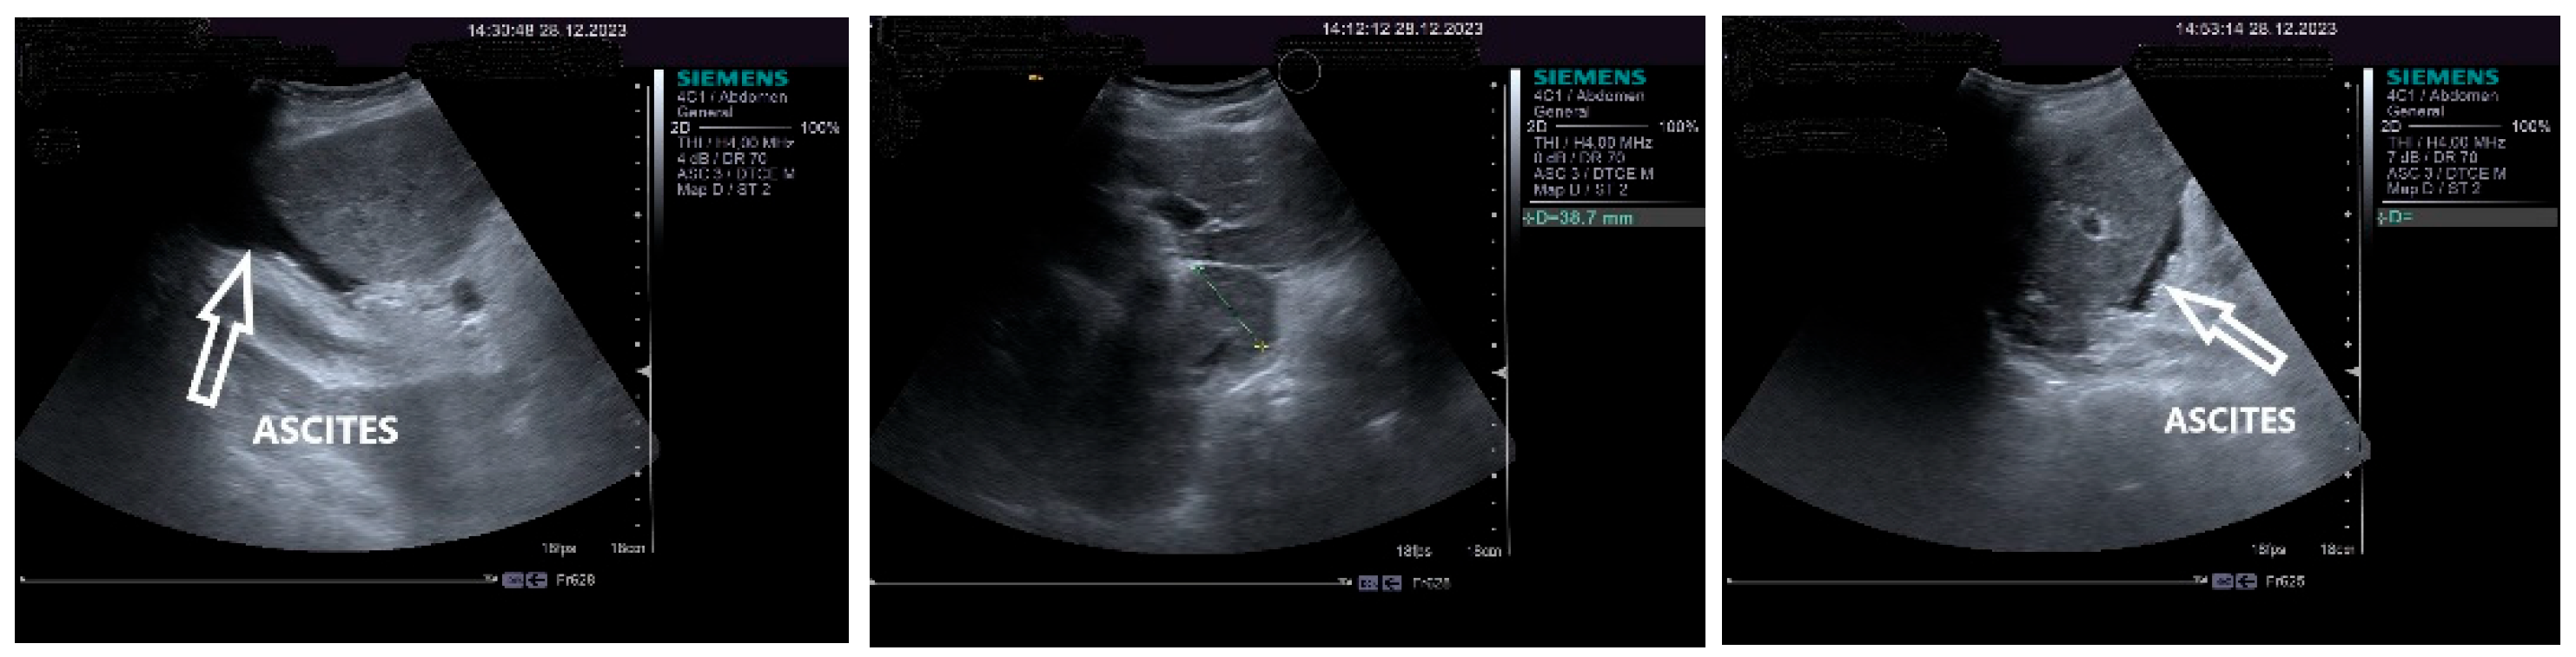

On physical examination, a mild tenderness of the right upper abdominal quadrant, a firm hepatomegaly, a palpable inferior pole of the spleen and a slight increase in abdomen volume were found. No other liver stigmata were noticed. The abdominal duplex ultrasound examination, performed with Siemens high-resolution equipment, showed hepatomegaly with a discrete irregularity of the liver surface, heterogeneity of the liver texture, the caudate lobe at the upper limit, filiform hepatic veins, massive thickening of the gallbladder wall, ascites in small quantity and mild splenomegaly with turbulence of the venous flow in the hilum. The question about liver cirrhosis was asked. Various aspects of the 2D ultrasound examination of the liver are depicted in Figure 2.

Figure 2. The 2D ultrasound aspect of the liver: perihepatic ascites (right,left), caudate lobe at the upper limit (middle).